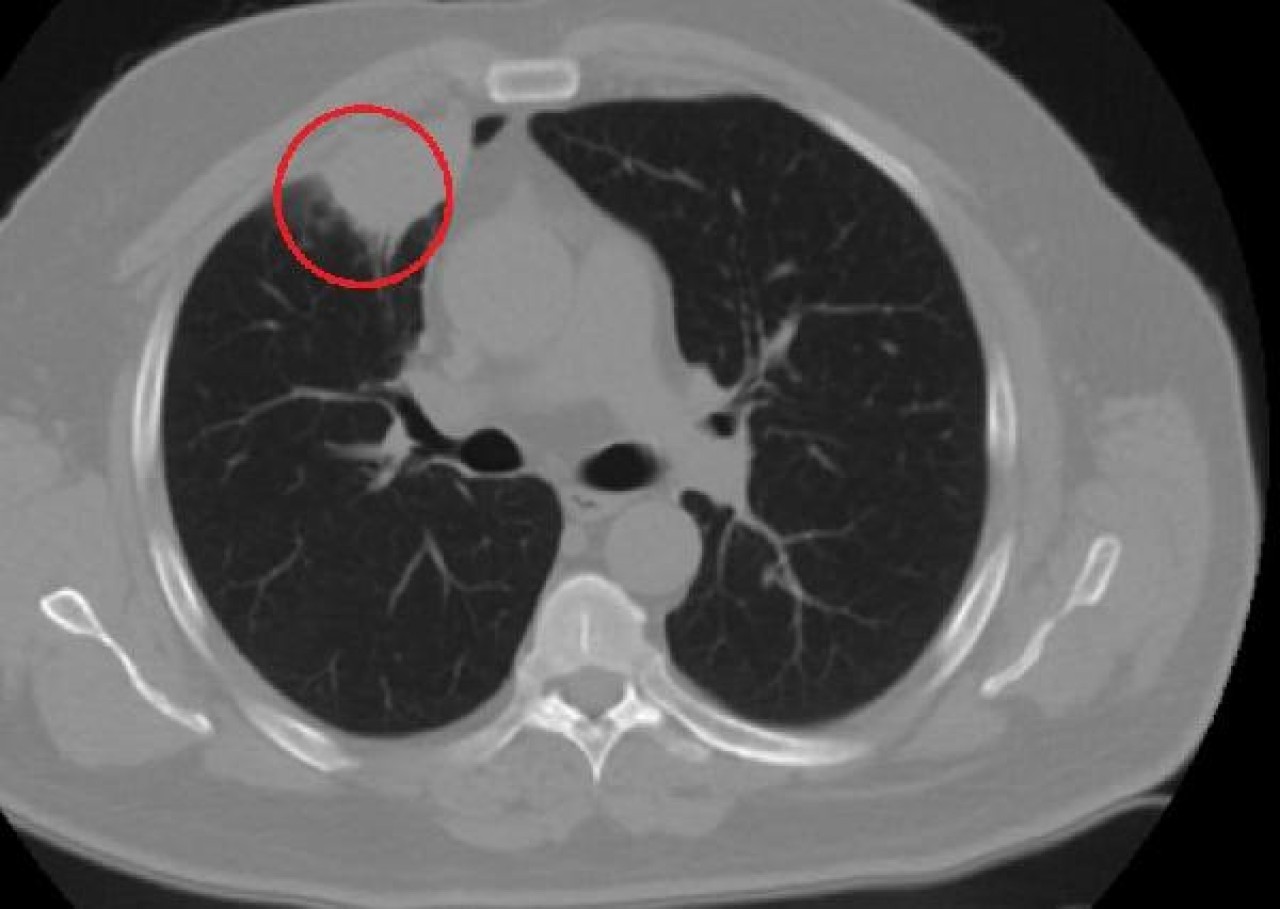

"Hastamız, çalıştığı başka bir kentte göğsünden darbe alıyor ve ağrıları geçmeyince bir üniversite hastanesine başvuruyor. Burada hastaya bir akciğer grafisi çekiliyor. Sağ akciğerinde bir kitleye rastlanıyor. Daha sonra hastaya, bir akciğer tomografisi çekiliyor ve göğüs cerrahisi için önemli büyüklükte olan 4 santimetre çapında, akciğer kanserine benzer özellikte radyolojik bulgular olan bir kitle tespit ediliyor. Daha sonra hastaya yapılan ileri tetkiklerde akciğer kanseri teşhisi konuluyor. Hastaya bir cerrahi planlanıyor. Hasta Kahramanmaraşlı olduğu için kendi memleketine gelmeyi tercih ediyor. Bize başvurdu ve göğüs ağrısı şikayeti vardı. Öksürük, nefes darlığı, balgam çıkarma, ateş gibi şikayetleri yoktu. Hastayı biz de değerlendirdik ve ameliyat olmasına karar verdik. Çünkü akciğer kanserine çok benzer radyolojik bulguları vardı. Sağlık Bakanlığımızın kuralları gereği her hastayı ameliyat öncesi PCR testi yapılır. Biz de ameliyat gecesi hastadan PCR testi aldık ve testi pozitif geldi. Ameliyatımızı 14 gün erteledik ve hastamıza koronavirüs tedavisi uygulandı. Hasta 14'üncü gün tekrar bize başvurdu ve yapılan PCR testi negatif çıktı. Yeni bir tomografi çektik ve tümörün tamamen ortadan kalktığını gördük. Şimdi sonuç bilgilerinden başlangıca gittiğimizde, bu bir akciğer kanseri olsaydı, ortadan kalkması mümkün değildi. Başka bir patolojiye bağlı durum olsaydı, yine verdiğimiz tedaviyle ortadan kalkmasını çok beklemeyiz. Antiviral tedavisi verdik ve hastanın radyolojik bulguları neredeyse tamamen normale döndü. Hastaya bunu izah ettik, 'Dünya literatüründe hiç görülmeyen bir radyolojik bulgu' diyerek. Bu gördüğümüz manzara artık hastanın akciğer grafisinde yok, akciğer kanseri değil. "

Hastayı takip etmeye devam ettiklerini belirten Kozanlı, 2 yıldır dünyayı etkisi altına alan koronavirüsün akciğer kanserini taklit ettiğini, böyle bir durumla ilk defa karşılaştıklarını söyledi. Hem Türkiye'de hem de diğer ülkelerde buna benzer bir vakanın olup olmadığını araştırdığını ifade eden Kozanlı, "Genel olarak dünya literatürüne baktığımızda koronavirüsün akciğer bulguları, radyolojik bulguları infiltrasyon, buzlu cam dansitesi gibi bilinen bulgular. Ama bizim hastamızda akciğer tümörünü taklit eden bir kitle vardı. Ve biz bunu dünya literatüründe hiç görmemiştik. Bununla ilgili geniş çaplı bir araştırma yaptım. Hem kendi deneyimlerimden hem kendi hastanemizde yatan hastalardan yola çıkarak birçok hastanın radyolojik bulgularına baktık. Dünya literatürlerini karıştırdım, diğer arkadaşlarıma danıştım, benzeri bulguya rastlamadım" diye konuştu.